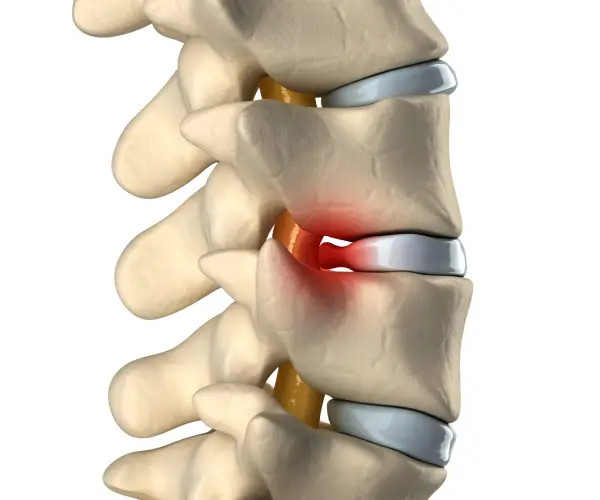

Stages of disc herniation

Cervical and Lumbar disc bulge